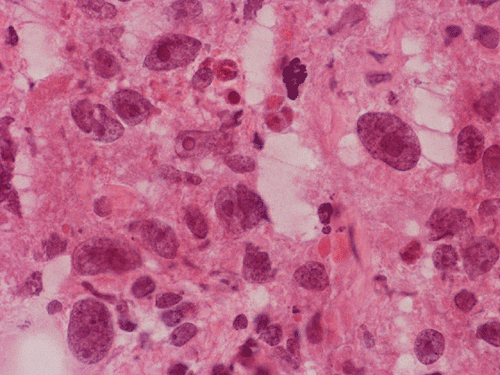

The volume of tissue received for examination amount to an aggregate of 4.0 x 2.0 x 1.5 cm in combined size. Grossly, the tissue is soft and has a creamy color with hemorrhage. The intraoperative cytologic preparation demonstrate a neoplasm composed with small to medium sized blue cells that smear out rather homgeneously and evenly. If you pay attention, there are some larger cells with a substantial amount of cytoplasm even at low magnification (Panel A). On high magnification, the nuclei are rather uniformly large, with high grade of pleomorphism, and almost all cells contain a distinct nucleoli. Apoptotic bodies and mitoses are frequent (Panel B). There are also large cells with prominent nucleoli and substantial amount of eosinophilic cytoplasm. These cells are suggestive of rhabdoid cells but none of them have the distinct inclusion body like cytoplasmic eosinophilic body of the rhabodid cells in atypical teratoid rhabodid tumor (Panel C). In the frozen section, both small to medium sized cells and cells with large nuclei with large, prominent, and eosinophilic nucleoli (Panel D and E). In the permanent sections, there is extensive necrosis (Panel F). The histology is in general agreement with that of frozen section except that the tumor cells appear to have more cytoplasm and more plemorphic, large nuclei with prominent nucleoli in comparison to the frozen section (Panel G). Large cells with substantial volume of cytoplasm, large, bizarre nucleoli and prominent, eosinophilic nucleoli are also noted (Panel H). There is a generalized degree of high grade pleomorphism. Results of immunohistochemistry are as follow:

Large cell and anaplastic medulloblastomas are recognized as different variants in the new WHO classficiation 1. They share many basic features with medulloblastoma 2, 3. The most notable differences are large cell size, increased variation of nuclear size, prominent and even eosinophilic nucleoli, increased mitotic figures and number of pyknotic or apoptotic cells, and extensive, geographic areas of necrosis. In the experience of the authors, most of the tumor cells in large cell and anaplastic medulloblastomas have high nuclear to cytoplasmic ratio in a manner similar to that of the classic variant. As per the new WHO classification, large cell medulloblastomas are composed mainly of large cells with more cytoplasm than the classic variant or the anaplastic variant. In the experience of the authors, this distinction is not always possible. The case being illustrated here includes some large cells with substantial amount of cytoplasm and but these cells only represent a portion of the tumor cell population. In general, anaplastic and large cell medulloblastomas have less favorable prognosis than the classic variant of medulloblastoma. However anaplastic changes are uncommon and does not affect the prognosis in adult cases as per one study 4.

ATRT shares many features with large cell (anaplastic) medulloblastomas. First, most of them occur in infants and children but ATRT are a lot more common in children under three years of age. Both tumor are highly malignant. In fact, the rapid growth as documented in this case lead to the consideration of ATRT before surgery. Second, both entities are featured by large cells with large nuclei and prominent nucleoli. During frozen sections, it may be a difficult task to distinguish these tumors. The rhabdoid cells in ATRT my not be very characteristics and a medulloblastoma like component is not uncommon in ATRT. Also, the rhabdoid cells may not be that numerous and the pathologist has to search for them. The intraoperative cytologic preparations provide excellent cytologic and nuclear details. In general, cells of large cell medulloblastoma do not have the typical eccentric nuclei and cytoplasmic inclusion like bodies in comparison to ATRT. In addition, although the nucleoli are large, they are not as prominent and eosinophilic as in ATRT. Third, cells of ATRT tend to be more intact and large cell (anaplastic) medulloblastomas tend to have predominantly naked nuclei. Distinction of the two entities on permanent sections is usually not a major problem. It should be noted that ATRT are polyphenotypic. However, they are usually positive for EMA which is typically negative in medulloblastoma and its variants. The greatest help would be immunohistochemistry for BAF-47. This antibody recognizes the protein coded by INI1 gene which is the critical gene on chromoome 22q11.2. This gene is expressed in normal tissue as well as neoplastic tissue except in the tissue where this gene is deleted and ATRT is the prototype 9. In some cases of ATRT, the staining can be patchy. The genetic deletion can be confirmed by fluorescent in situ hybridization. In a minority number of cases, no chromosome 22q11.2 deletion is demonstrated. The gene can be sequence in order to search for mutation of the INI1 gene.